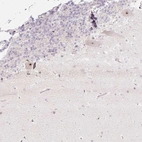

Immunohistochemical staining of human cerebellum shows strong nucleolar positivity in Purkinje cells.